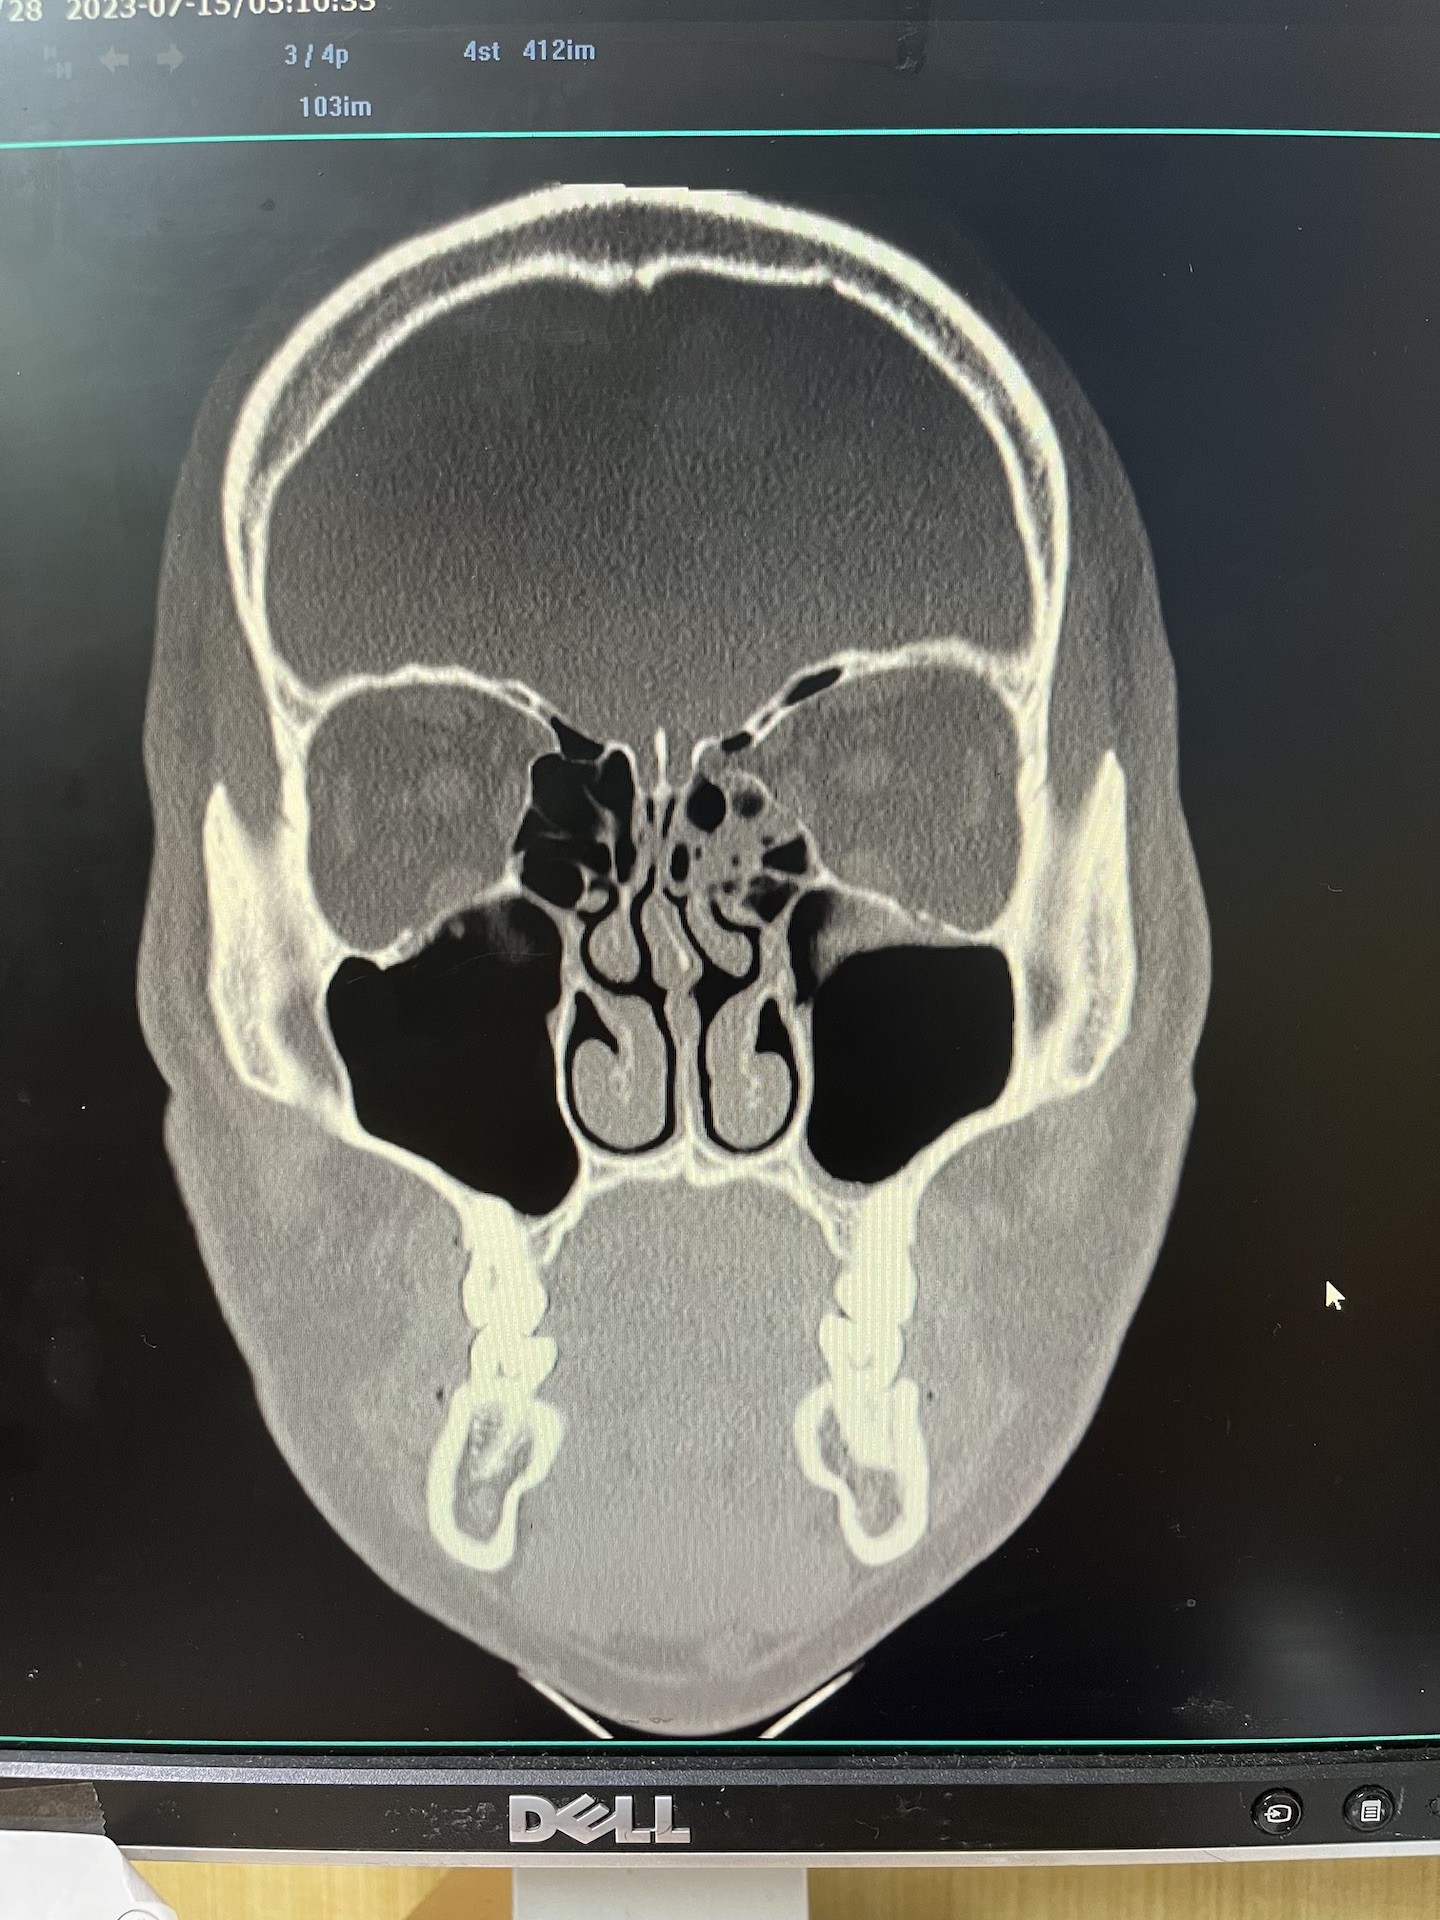

아래 제가 궁금한 사항입니다. 1. CT 사진 보셨을 때 안와골절 수술 여부에 대해 선생님 생각은 어떠신가요?

1. CT 사진 보셨을 때 안와골절 수술 여부에 대해 선생님 생각은 어떠신가요?

안와골절의 수술 적응증은 골절로 인한 증상이 없는 경우에 골절 크기가 내벽이나 하벽의 50% 이상으로 대략 잡고 있습니다.

첫번째 CT coronal plane 에서는 괜찮은듯 한데, 두번째 axial plane CT 에서는 50%를 넘어가는 듯 한데 애매하네요.

한달이 지나서 안구함몰이 없다면 앞으로 안구함몰이 생길 가능성은 희박하며, 보통 3개월이 경과해서는 더이상 진행하지는 않습니다. 지금은 수술에 대한 고민은 하지 않으셔도 될 듯 합니다.